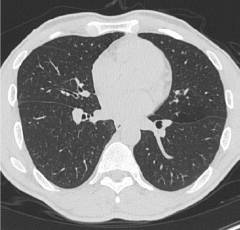

Гранулематоз Вегенера – системный васкулит, при котором поражаются мелкие сосуды органов дыхания и почек. Заболевание возникает у мужчин и женщин с одинаковой частотой. В среднем его начало приходится на возраст 40 лет.

- симптомы поражения легких;

- Локальный: поражение захватывает только верхние дыхательные пути.

- Ограниченный: поражение захватывает верхние дыхательные пути и легкие. При этом сосуды почек не страдают.

- Генерализованный: отмечается поражение легких, верхних дыхательных путей и почек.

| Поражение легких |

|